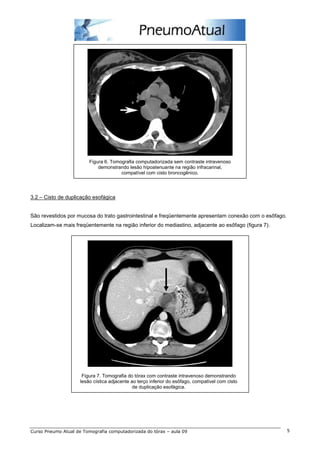

Lesão congênita correspondendo a cerca de 60% dos cistos de duplicação do intestino anterior. Na TC

estes cistos geralmente são arredondados, têm contornos lisos e bem definidos, com paredes finas e

atenuação variável, dependendo da composição (figura 6). Podem ser encontrados em qualquer região do

mediastino, porém são mais comuns no mediastino médio e posterior, próximos à carina e na região

paratraqueal.

Figura 6. Tomografia computadorizada sem contraste intravenoso

demonstrando lesão hipoatenuante na região infracarinal,

compatível com cisto broncogênico.

3.2 – Cisto de duplicação esofágica

São revestidos por mucosa do trato gastrointestinal e freqüentemente apresentam conexão com o esôfago.

Localizam-se mais freqüentemente na região inferior do mediastino, adjacente ao esôfago (figura 7).

Figura 7. Tomografia do tórax com contraste intravenoso demonstrando

lesão cística adjacente ao terço inferior do esôfago, compatível com cisto

de duplicação esofágica.